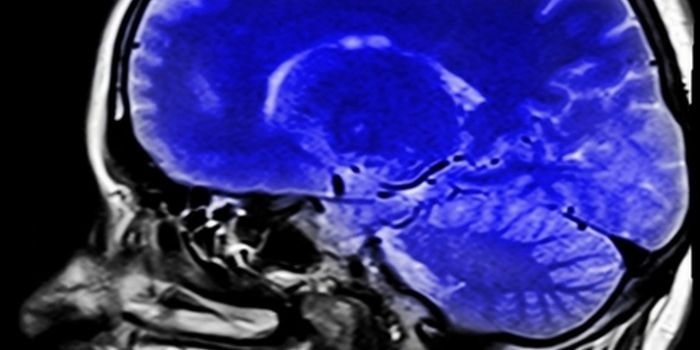

MAR 20, 2018NeuroscienceIf someone were to say, "He is such an air head" or "He's lost his mind" that would be considere ...

DEC 03, 2018NeuroscienceIdentifying the connection between the brain size to smartness has become much more plausible due to accuracy in estimat ...

DEC 13, 2019Genetics & GenomicsPeople who carry certain mutations in gene CHD8, a gene strongly linked to autism, tend to be taller and have larger hea ...